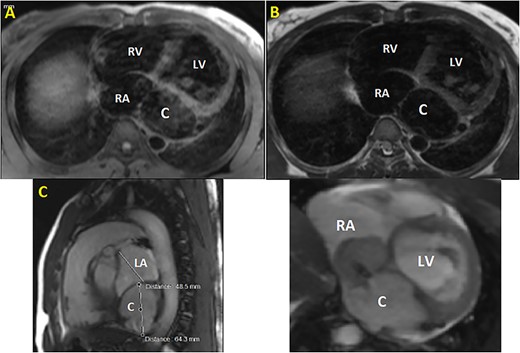

Initial physical examination showed stable vital signs. Auscultation found systolic murmurs of mitral and tricuspid regurgitations. There were no peripheral edema or other signs of heart failure. Abdominal examination revealed no tenderness, hepatomegaly or ascites. Electrocardiogram at admission showed sinus rhythm with no conduction abnormalities or signs of ischemia. Chest radiograph found an enlargement of the cardiac silhouette. Routine blood tests were normal. Transthoracic echocardiography (TTE) found a bi-atrial cystic structure, which we initially suspected to be a hydatid cyst as cystic echinococcosis is highly endemic in Morocco. Color Doppler showed a massive shunt with blood coming into the right atrium (RA) from an unknown source (Fig. 1). Cardiac magnetic resonance imaging (CMR) showed a bilobed cystic lesion hypointense on T1 and T2 sequences, with the same signal as cardiac chambers, located below and behind the left atrium (LA). The superior lobe was 48-mm wide and the inferior lobe 65-mm wide. On the peripheral wall of this structure, a giant circumflex artery (LCX), with a right atrial shunt, was present (Fig. 2). Coronary angiography (CA) along with computed tomography angiography (CCTA) confirmed the bilobed circumflex saccular aneurysm and CAF (Figs 3 and 4).

CMR. (A) T1 sequence showing a cystic hypointense lesion, with the same signal than cardiac chambers, located below and behind the LA; (B) T2 sequence showing the hypointense lesion; (C) vertical long axis view showing the bilobed lesion; (D) cine imaging showing an aneurysmal circumflex artery with a right atrial shunt. RV, right ventricle; LV, left ventricle; C, cystic lesion.